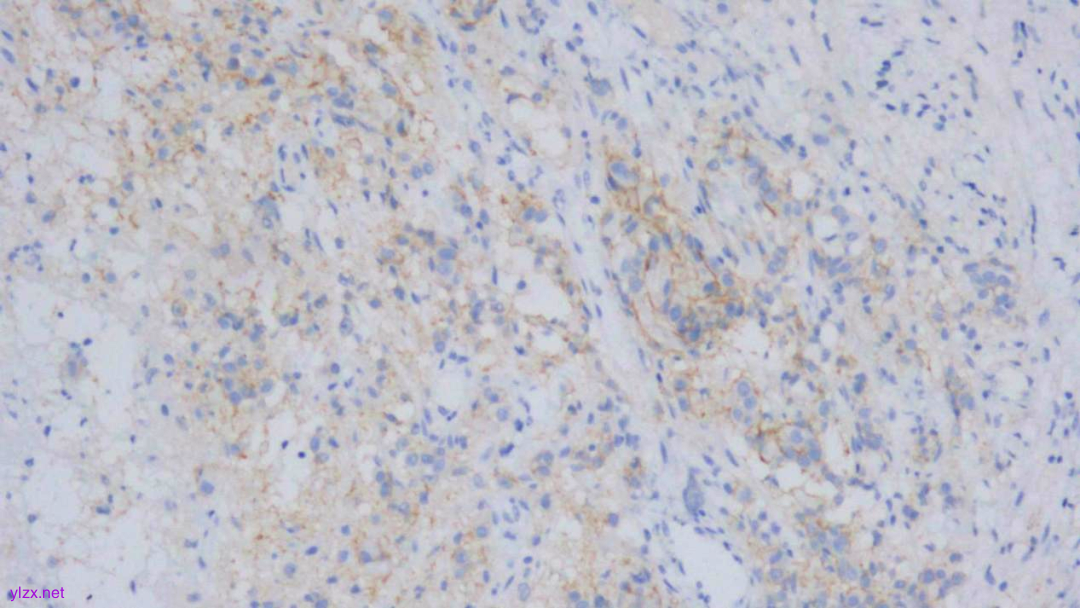

IHC结果:

CK(AE1/AE3)(+)、GATA3(+)、P120(浆+)、E-Cadherin(-)、CK7(+)、CK-H(+)、CAM5.2(+)、CK20(-)、CEA(poly)(-),P53(约40% 弱+),Ki-67(约1%+)

AE1/AE3(弥漫强+)

GATA-3(+)

P120(浆+)

E-Cadherin(-)

CEA(少量+)

CK7(弥漫强+)

ki-67(个别细胞+)

(胃窦)腺癌,HE形态结合临床病史、免疫组化结果,符合乳腺浸润性小叶癌转移。